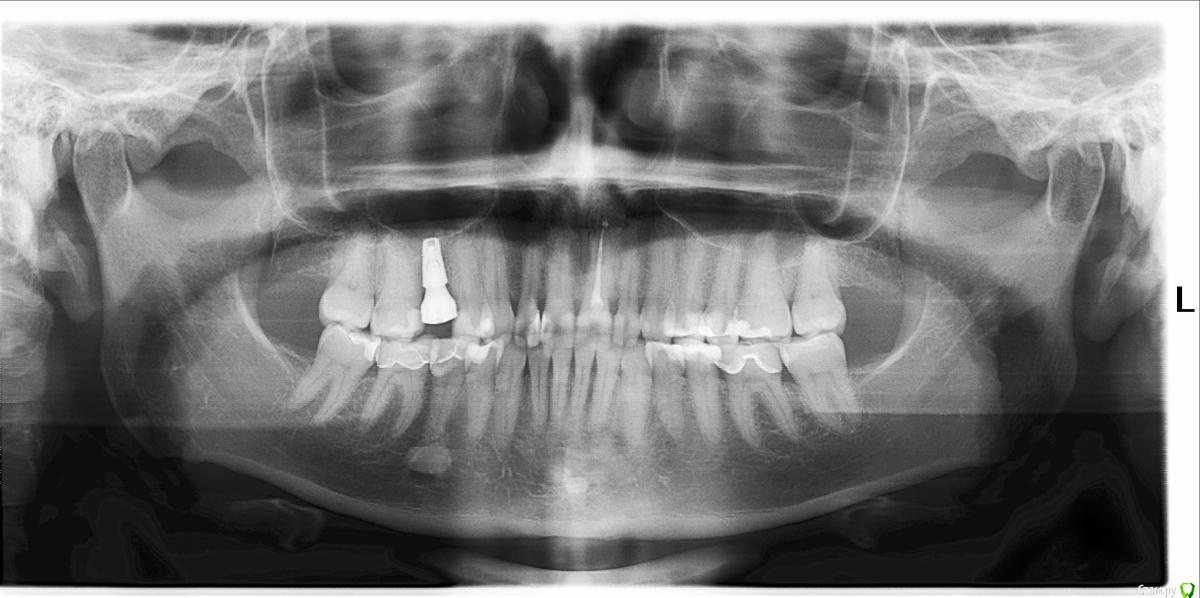

Illina Опубликовано 5 августа, 2019 Поделиться Опубликовано 5 августа, 2019 Добрый день!Несколько дней назад откололся кусочек пломбы на переднем зубе снизу (самой пломбе около полутора лет).Пломбы там огромные, я боюсь переделывать их просто негде, от зубов там совсем мало((( Можно ли просто восстановить этот кусочек пломбировочным материалом? т.е. пломбу на пломбу? Также на двойках на стыке пломб и зубов есть 2 пятнышка небольших коричневых, заметила около месяца назад - в прошлый раз врач из зашлифовала, перестали быть видны примерно на год хватило эффекта. Можно ли зашлифовать опять или на ваш взгляд надо переделывать? В связи с переездом пока непонятно, к кому лучше обратиться... Ссылка на комментарий

red_butler Опубликовано 5 августа, 2019 Поделиться Опубликовано 5 августа, 2019 зуб нужно протезировать искусственной коронкой Ссылка на комментарий

Illina Опубликовано 5 августа, 2019 Автор Поделиться Опубликовано 5 августа, 2019 Так получилось, что я уже имею 1 имплант там, где поставила коронку... Она простояла года полтора, следующая около года... Достаточного размера основание для нее делать не получалось в том корне, который имелся, а небольшой высоты штырь этот не держал ее... В то же время аналогичный зуб, который во время еще первой беременности также рекомендовали под коронку из-за большого разрушения, до сих пор со мной (тьфу-тьфу) , а ребенок, которым была тогда беременна, уже студент) Не поймите меня неправильно, я очень ценю ваше мнение, просто очень страшно все, что передних зубов касается и хочется узнать - теоретически приделать кусок пломбы к пломбе возможно?Если нет, тогда буду морально настраиваться наверное на имплантацию сразу((( Ссылка на комментарий

dok1 Опубликовано 5 августа, 2019 Поделиться Опубликовано 5 августа, 2019 То, что другой зуб развалился - не показатель. На передний зуб нужна своевременная коронка, а не лепнина Ссылка на комментарий